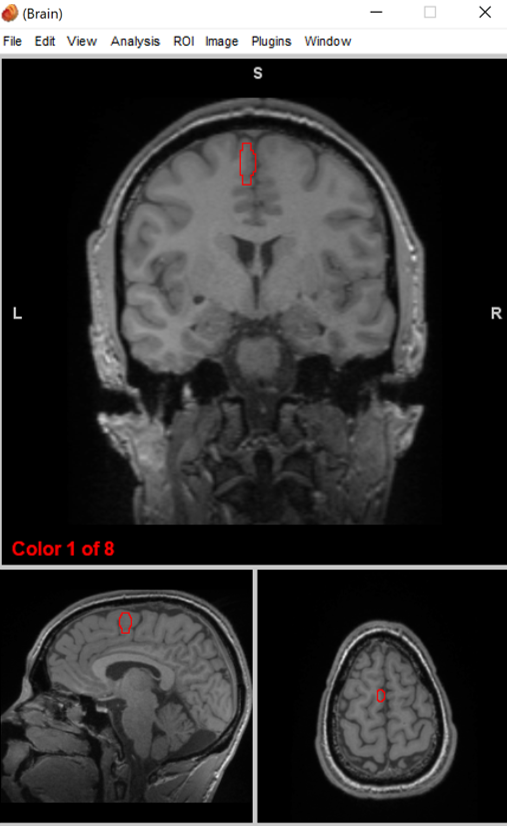

prefrontal cortex

judgement, inhibition,and decision making